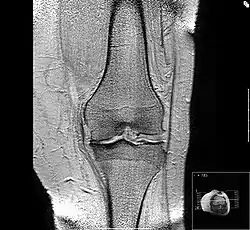

Annotated illustration of healthy hip joint

Healthy hip joint

Annotated illustration of hip joint with osteoarthritis

Hip joint with osteoarthritis[36]